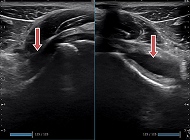

小児単純性

股関節炎

左右を比較すると関節内水腫の貯留が確認できます。

1歳

橈骨遠位端骨折

レントゲンでは分からない微小な骨折を認めます。

野球肘

左右を比較すると離断性骨軟骨炎の所見がはっきりわかります。